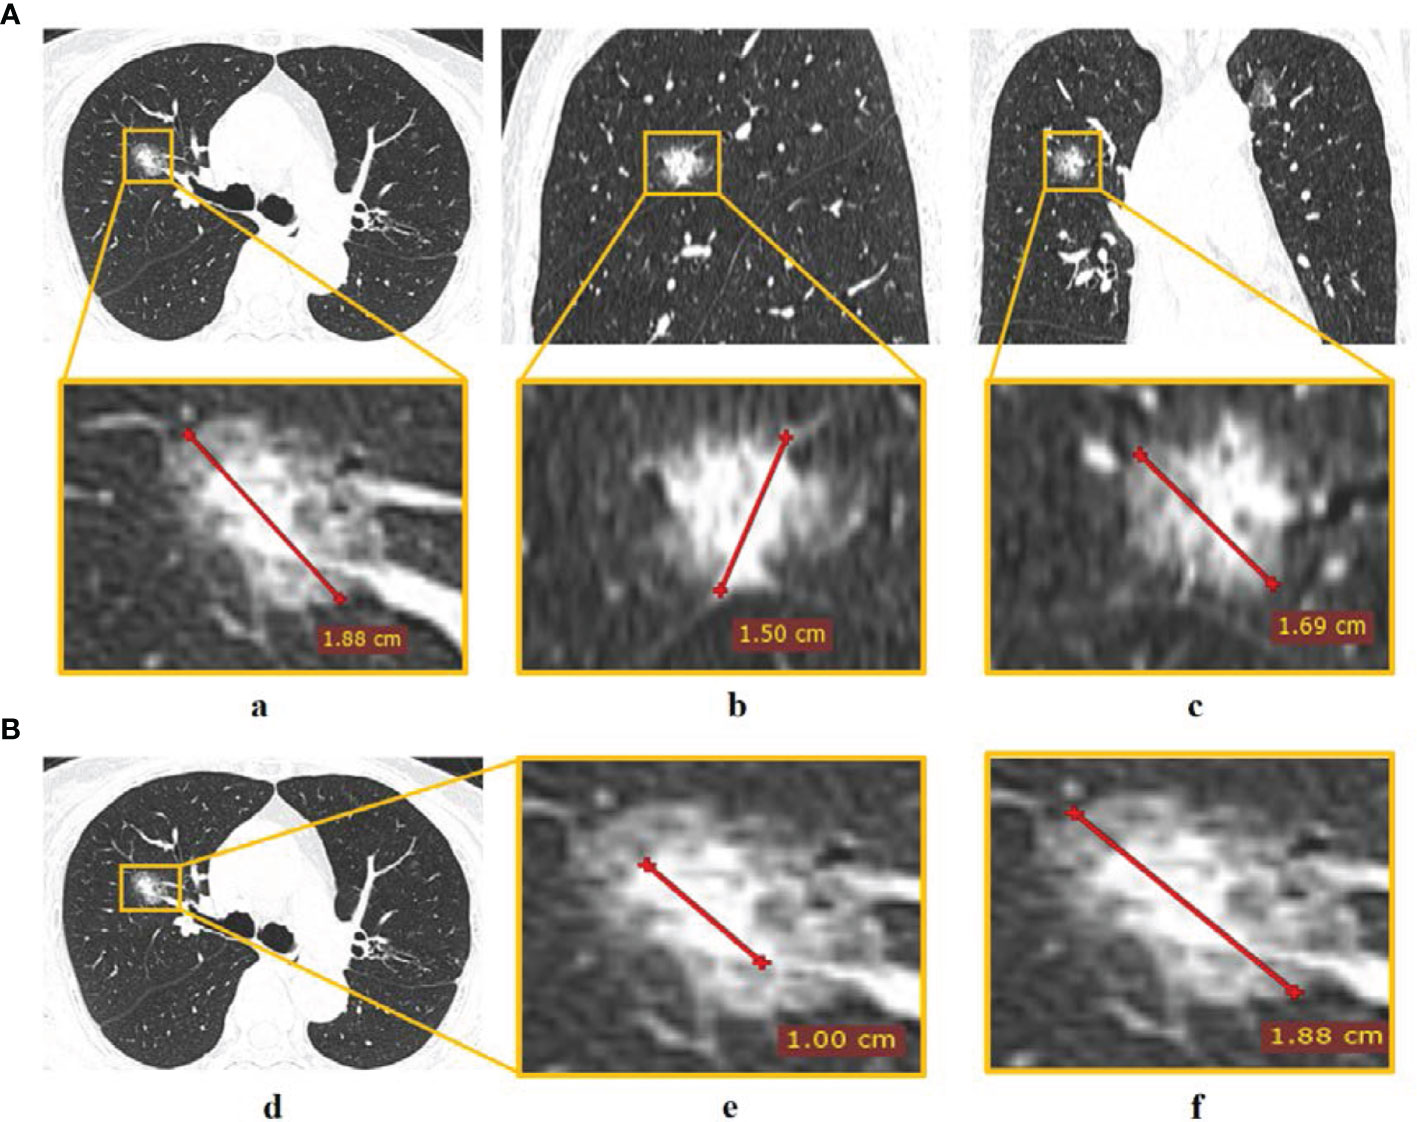

Two CT radiological features, namely, maximum tumor diameter (MTD) and the consolidation-to-tumor (C/T) ratio were extracted. MTD was defined as the largest tumor diameter among three planes (transverse, sagittal, and coronal) (Figure 2A) (23). C/T ratio was defined as the maximum consolidation (C) diameter divided by the maximum tumor (T) diameter in the transverse plane (Figure 2B). The details of PET/CT image acquisition, tumor segmentation, MTD and C/T ratio measurement, radiomics feature extraction, and inter-observer reproducibility analysis can be found in the Supplementary Information. The inter-class correlation coefficient (ICC) was used to evaluate the inter-observer reproducibility of MTD, C/T ratio, and radiomics features.

Figure 2 The measurement of CT radiological features. (A) Tumor diameter measured in (a) transverse, (b) sagittal, and (c) coronal planes, and the largest diameter in the three planes was defined as MTD; (B) C/T ratio measurement of (d) tumor via (e) maximum consolidation diameter divided by (f) maximum tumor diameter in the transverse plane.